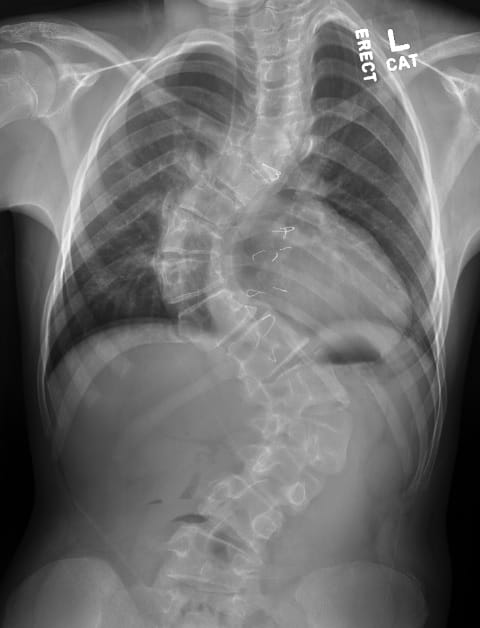

Preoperative scoliosisPreoperative scoliosis measuring greater than 80 degrees with congenital hemivertebra at T6.